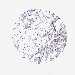

BRCA TCGA BRCA VALIDATION PROTEIN EXPRESSION

ANTIBODIES

AND

VALIDATION